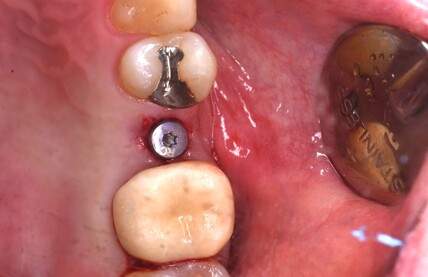

症例写真-2

- Befor

- 途中経過

- After

| 年齢 | 50代・男性 |

|---|---|

| 主訴 | 右下歯が疼く |

| 治療内容 | ・右下6番インプラント ※1:FGG(遊離歯肉移植術)とは、足りない歯ぐきを上顎から上皮を切り取り移植する外科手術 |

| 治療費 | 合計:902,000円(税込) ■内訳 |

| 治療期間 | 9ヵ月 |

| 治療方針 | 右下の当該歯は歯根破折により保存不可能と診断しました。歯周疾患も伴っていたため抜歯後に骨吸収※1が大きく起こることが予測できました。チタンメッシュ併用骨再生誘導法(GBR※2)を選択しインプラント埋入と同時に行い自然な歯槽骨のラインを再現しました。またGBRを行う際にインプラント辺縁の付着歯肉の減少が起こる為、遊離歯肉移植術(FGG※3)を行い清掃性を考慮した形態に仕上げました。 ■治療方針の解説 治療した右下の歯をレントゲンで撮影したところ根本の部分に黒く写る箇所があり「根尖性慢性周囲炎※1」と診断。また歯周病も進行していました。 ※1 骨吸収・・・歯槽骨という歯を支える骨がなくなっていくこと |

| 担当者所見 | 主訴の右下だけでなく歯茎の腫れ、発赤があり不良補綴や不良充填など他にも治療箇所が多数ありました。プラークコントロールが不良であった為まずはブラッシング指導を行いセルフケアの重要性を理解していただくところからスタートしました。 右下6番の歯はインプラント治療を行なった結果審美的にも機能的にも患者様の満足を得ることができました。骨造成と歯肉移植も行なった為インプラントを支える十分な歯周組織の獲得ができたと思っております。 |